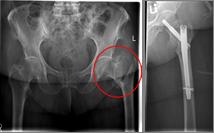

Pertrochanteric fractures, which are not femoral neck fractures close to the hip, are treated with a so-called gamma nail. The rupture here runs through the large and / or small "hillock" (trochanter major and minor) of the thighbone. Here, due to the location of the fracture, the blood supply to the femoral head is NOT compromised. After the operation, an immediate mobilization can take place under pain-adapted full load.

Picture: In this pertrochanteric femur fracture, a gamma nail was used to stabilize the fracture. The femoral head does not have to be replaced in this case, because the femoral neck is intact and the femoral head is still well supplied with blood.